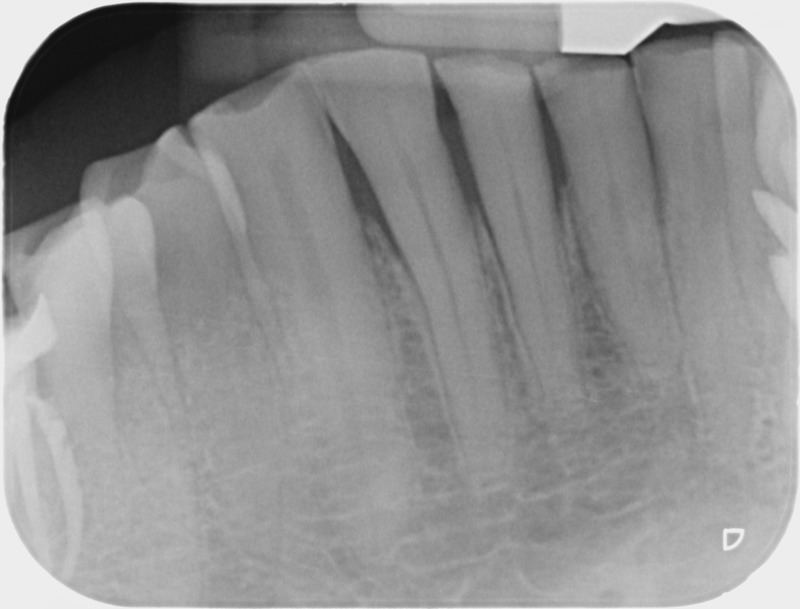

Avant

Après

• Traitement endodontique : Sous anesthésie locale et à travers la protection d’un champ opératoire nous accédons à la pulpe de la dent à soigner, puis aux canaux de ses racines que nous devons désinfecter. Ce soin nécessite l’élimination complète de la source de contamination (souvent la carie) parfois sous une ancienne reconstitution ou une couronne qu’il faut alors retirer. Une fois le nettoyage et la mise en forme des canaux réalisés, nous les obturons de façon hermétique avec un ciment et un matériau thermoplastique appelé Gutta Percha. Ceci afin d’empêcher une nouvelle prolifération bactérienne et d’assurer le maintien de la dent dans ses structures de soutien (ligament parodontal et os alvéolaire). L’ouverture effectuée au centre de la dent sera d’abord refermée avec un pansement provisoire avant d’envisager ensemble la reconstitution d’usage : un composite, un inlay-onlay ou une couronne.